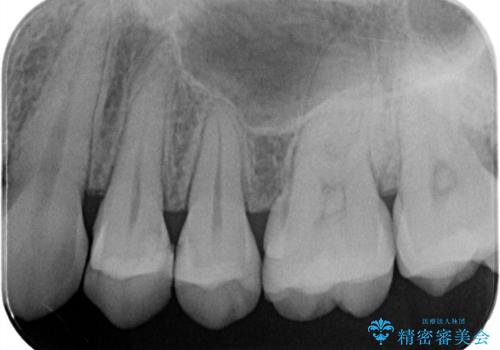

- 主訴:左上真ん中らへんの歯が欠けてしみるので治したい

左上4近心に実質欠損を認め、遠心から咬合面にかけてはCR修復が施されていたため、MODインレー窩洞としました。